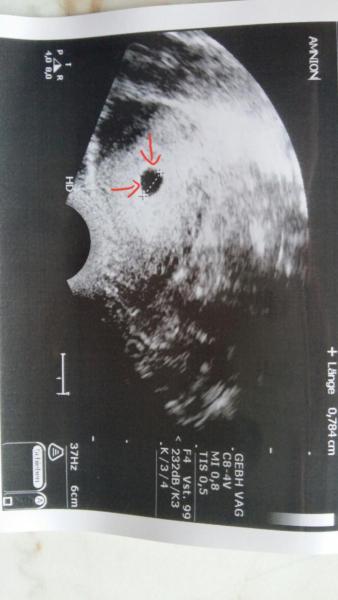

Antwort auf Beitrag von JenniLotte

So sah es bei mir in der 5/6 ssw aus. Das sind glaub ich Artefakte vom Ultraschall. Wäre iwas würde dein FA das mit dir besprechen.